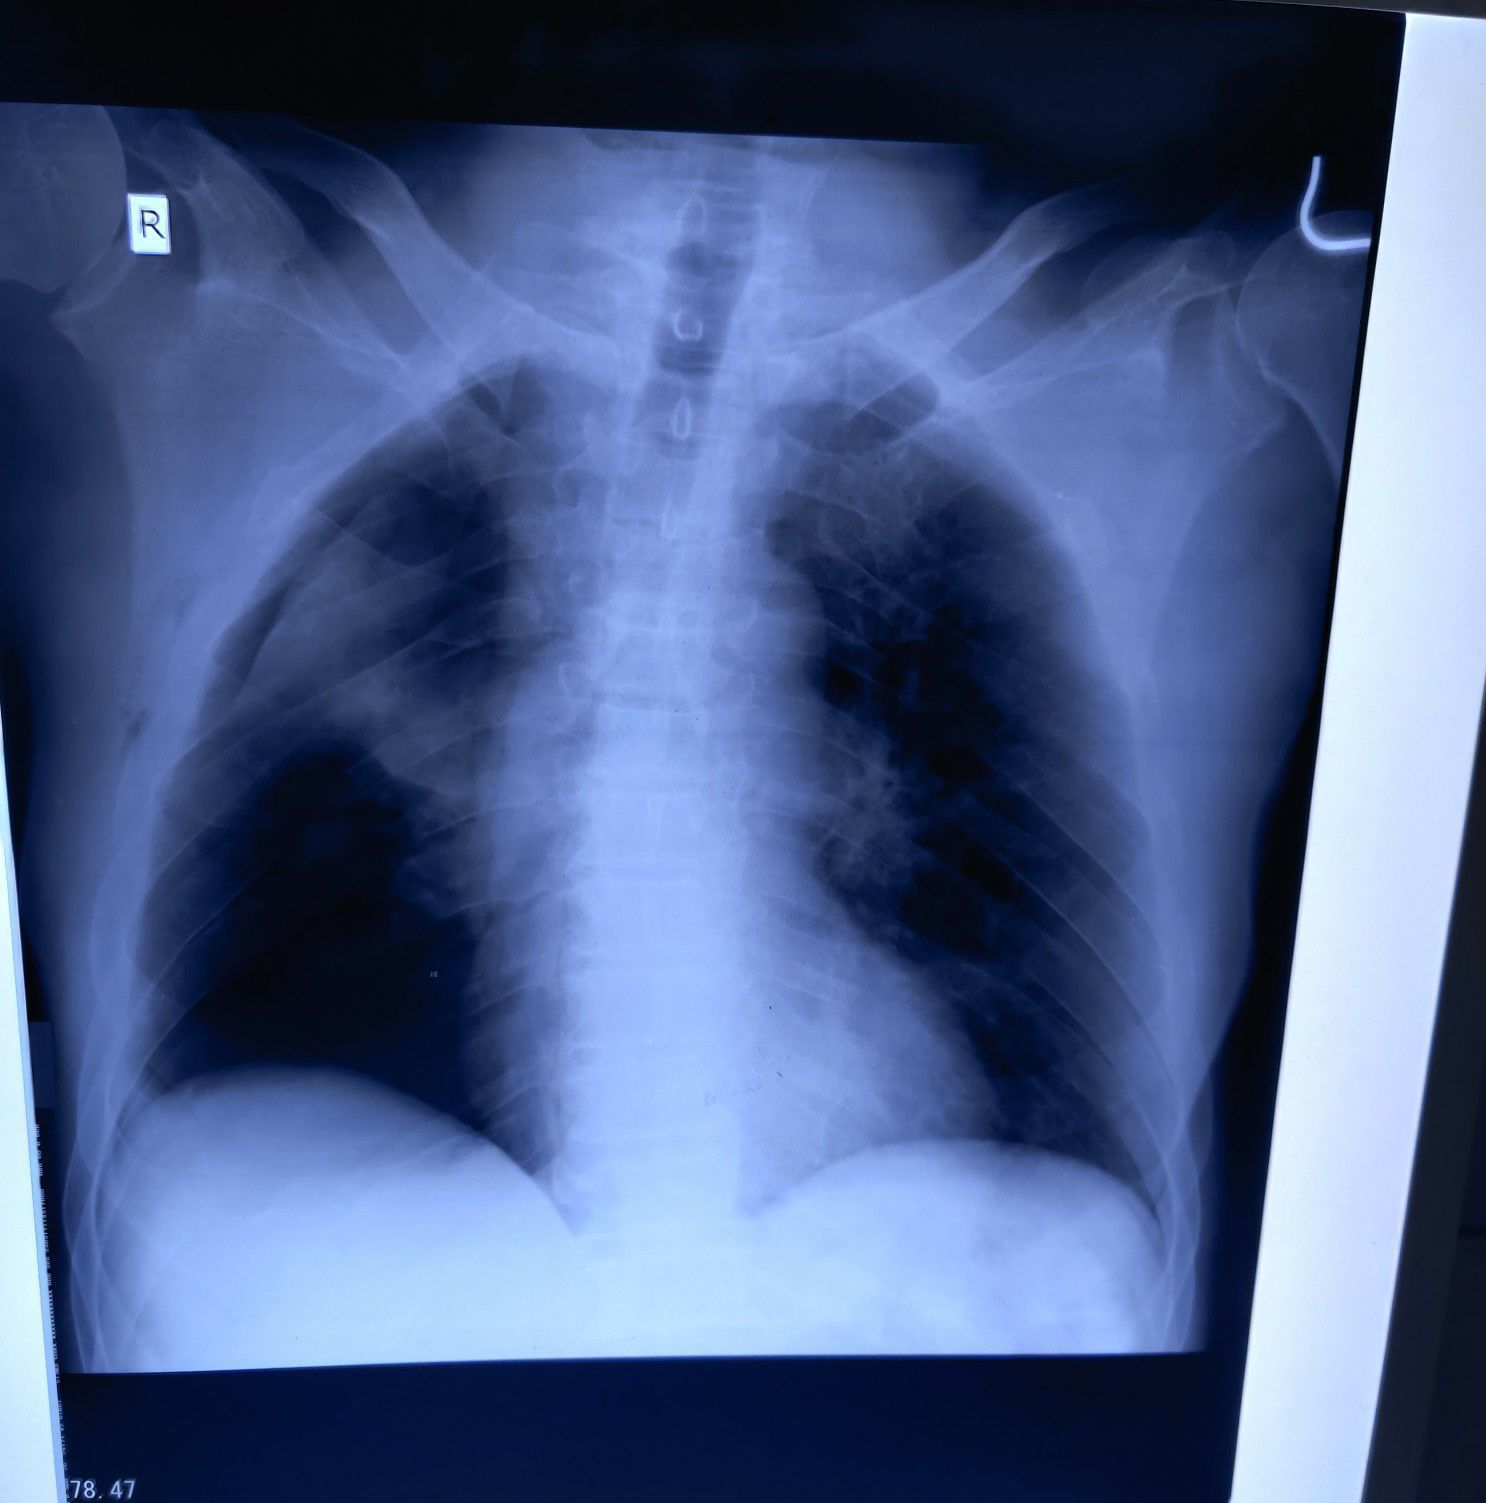

R sided pneumothorax

Chest

Pneumothorax

Rta